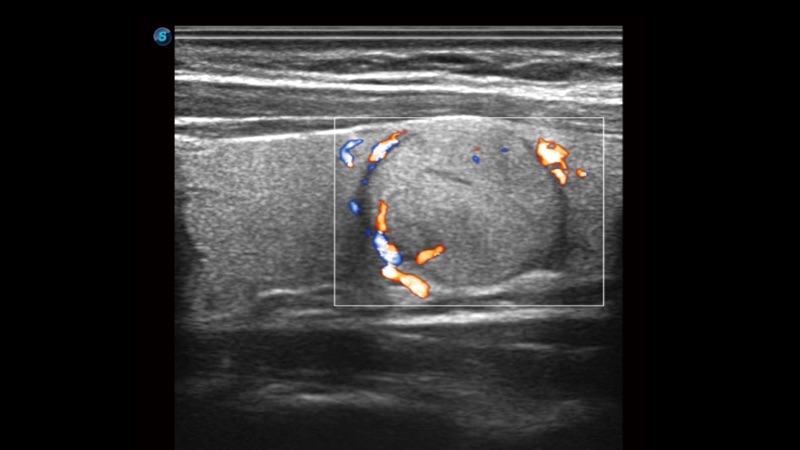

实时宽景成像技术

通过彩色血流和实时宽景相结合,可观察到完整的动静脉血流,方便医生检查。实时扫查过程中,如有任何操作失误也可以很容易地进行回扫擦除,而不会中断扫查。

临床图像